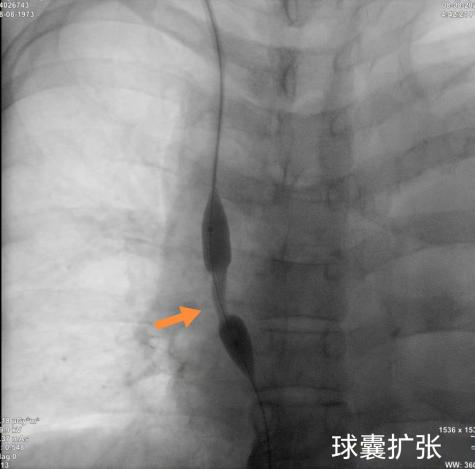

2)微创的"介入治疗"是治疗CVS的首选方式,包括球囊扩张(PTA)和支架置入(PTS);

球囊扩张:用一个小小的球囊把狭窄的血管"撑"开